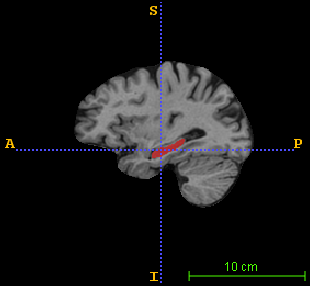

Over the past decades, state-of-the-art medical image segmentation has heavily rested on signal processing paradigms, most notably registration-based label propagation and pair-wise patch comparison, which are generally slow despite a high segmentation accuracy. In recent years, deep learning has revolutionalized computer vision with many practices outperforming prior art, in particular the convolutional neural network (CNN) studies on image classification. Deep CNN has also started being applied to medical image segmentation lately, but generally involves long training and demanding memory requirements, achieving limited success. We propose a patch-based deep learning framework based on a revisit to the classic neural network model with substantial modernization, including the use of Rectified Linear Unit (ReLU) activation, dropout layers, 2.5D tri-planar patch multi-pathway settings. In a test application to hippocampus segmentation using 100 brain MR images from the ADNI database, our approach significantly outperformed prior art in terms of both segmentation accuracy and speed: scoring a median Dice score up to 90.98% on a near real-time performance (<1s).